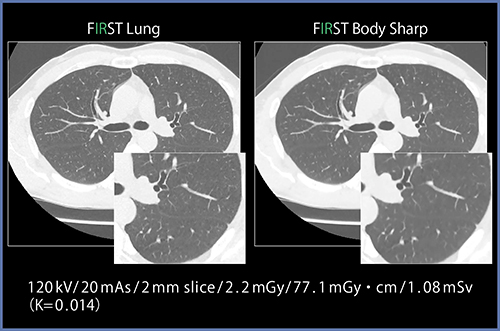

FIRSTでは,Full IR内部のパラメータを部位別に最適化することで,臨床目的,対象部位に合わせた最適な調整パラメータの選択(図5)や,3種類の強度(Mild,Standard,Strong)からノイズ低減率の選択が可能です(図6)。

現時点でLung(肺野),Body〔軟部組織(ノイズ低減優位)〕,Body Sharp〔軟部組織(粒状性,先鋭度優位)〕,Cardiac(心臓全般),Cardiac Sharp〔心臓(冠動脈内腔,先鋭度優位)〕,Bone〔骨(四肢,耳小骨など)〕の6種類の部位別パラメータがあり,さらに頭部パラメータについても現在開発を進めています。頭部領域では,ビームハードニング対策,コーンビームアーチファクト対策,低コントラスト改善を目的として調整を進めています。

図5 対象部位に合わせた最適化パラメータの適用